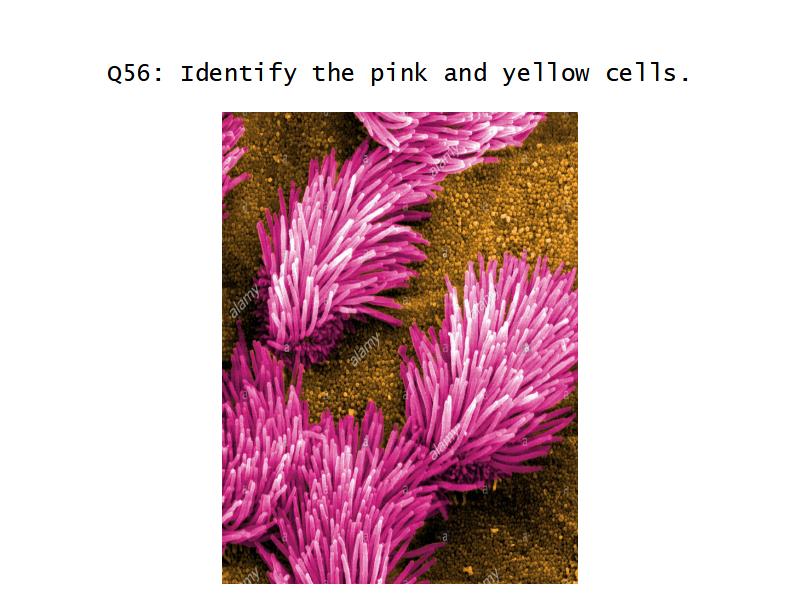

- Ciliated columnar cells

- Non-ciliated columnar cells

- Goblet cells

- Basal cells

- Ciliated columnar > Ciliated cuboidal

- NO glands - goblet cells -> secretory cells

- Ciliated cuboidal epithelium

- Secretory cells